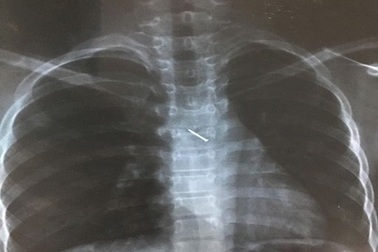

Đinh ghim găm vào phế quản bé trai 6 tuổiChiều 3/5, BS.Ths Trần Văn Học, trưởng phòng Kế hoạch tổng hợp (BV Nhi TƯ cho biết), bệnh viện vừa nội soi lấy đinh ghim nằm sâu trong phế quản một bệnh nhi.